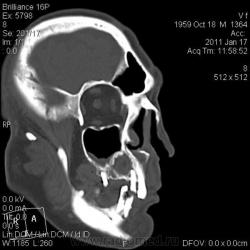

КТ головного мозга. Случайная находка. Жалоб "на челюсти" нет.

Мужчине 51 год. Периферический рак легкого. Очаговых изменений головного мозга не нашла. Пациент не критичен к своему состоянию (никуда не поеду, пусть как есть остается), поэтому отсутствие жалоб еще ничего не значит.

Контуры внутренние деструктивной полости изъеденные, кость вздута, но внешне не видно. В центре уровень?  с плотностью 30 ед.Н. Адамантинома? С зубными делами практически не сталкиваюсь. Нужна Ваша помощь. Какие будут идеи, уважаемые коллеги?